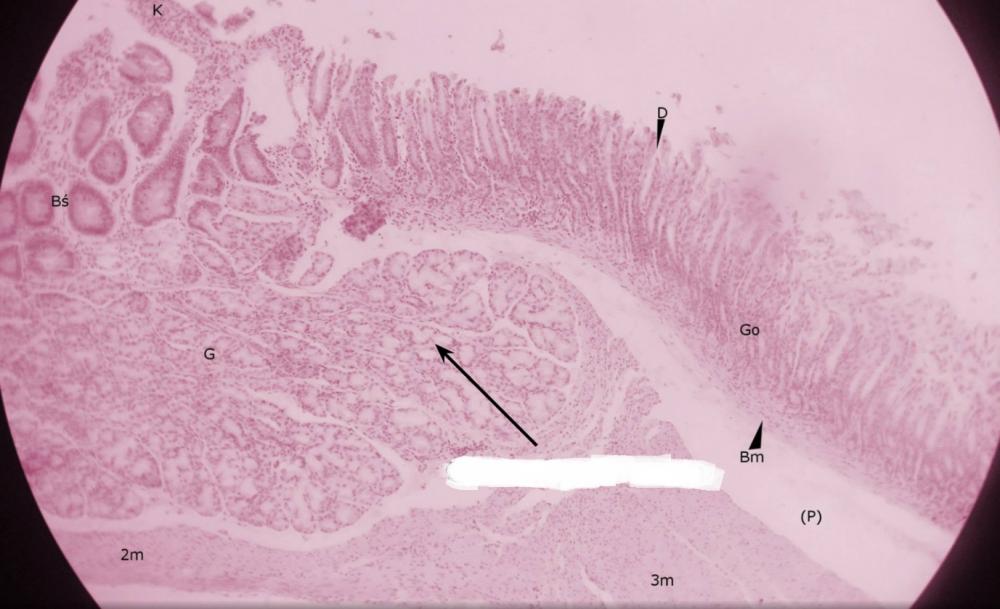

dołki żołądkowe (przejście żołądka w dwunastnicę)

pólka żołądkowe (przejście żołądka w dwunastnicę)

rozgałęzione gruczoły cewkowe - odźwiernikowe (przejście żołądka w dwunastnicę)

kosmek jelitowy (przejście żołądka w dwunastnicę)

krypta jelitowa (przejście żołądka w dwunastnicę)

gruczoły Brunnera (przejście żołądka w dwunastnicę)

błona mięśniowa, składająca się z warstwy okrężnej o podłużnej (przejście żołądka w dwunastnicę)

miejsce po błonie podśluzowej (przejście żołądka w dwunastnicę)

blaszka mięśniowa błony śluzowej (przejście żołądka w dwunastnicę)

gruba, trójwarstwowa mięśniówka żołądka (przejście żołądka w dwunastnicę)